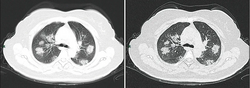

From the CT scans of COVID-19 infected lungs, white patches were observed containing fluid known as ground-glass opacity (GGO) or simply ground glass.[130] This tended to correlate with the clear jelly liquid found in lung autopsies of people who died of COVID-19. One possibility addressed in medical research is that hyuralonic acid (HA) could be the leading factor for this observation of the clear jelly liquid found in the lungs, in what could be hyuralonic storm, in conjunction with cytokine storm.[131]

Imaging

Chest CT scans may be helpful to diagnose COVID‑19 in individuals with a high clinical suspicion of infection but are not recommended for routine screening.[175][187] Bilateral multilobar ground-glass opacities with a peripheral, asymmetric, and posterior distribution are common in early infection.[175][188] Subpleural dominance, crazy paving (lobular septal thickening with variable alveolar filling), and consolidation may appear as the disease progresses.[175][189] Characteristic imaging features on chest radiographs and computed tomography (CT) of people who are symptomatic include asymmetric peripheral ground-glass opacities without pleural effusions.[190]

Many groups have created COVID‑19 datasets that include imagery such as the Italian Radiological Society which has compiled an international online database of imaging findings for confirmed cases.[191] Due to overlap with other infections such as adenovirus, imaging without confirmation by rRT-PCR is of limited specificity in identifying COVID‑19.[190] A large study in China compared chest CT results to PCR and demonstrated that though imaging is less specific for the infection, it is faster and more sensitive.[174]